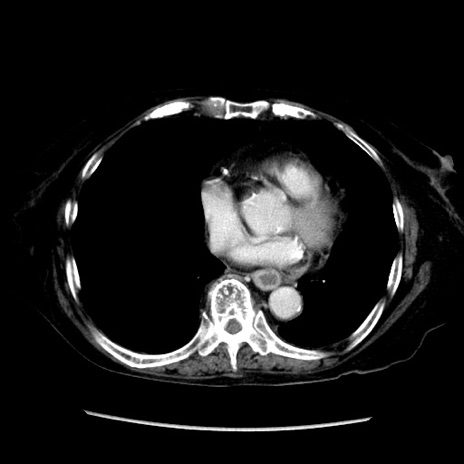

冠状断像

【症例】 90歳代女性

【主訴】 腹痛・嘔吐

【現病歴】今朝から左側腹部痛を認めた。 経過観察していたが、嘔吐を認めたため来院。

【既往歴】 子宮癌術後

【身体所見】 意識清明、BP 127/54mmHg、P 98bpm Sp02 95%(RA)、BT 35.8°C、腹部平坦・軟腸ぜん動音聴取良好、右下腹部圧痛(+) 反跳痛なし

【データ】WBC 9800、CRP 0.46